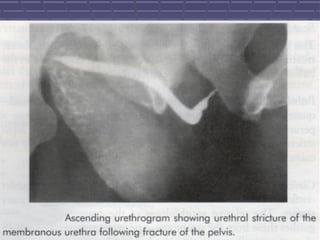

RADIOGRAPHIC EVALUATIONRADIOGRAPHIC EVALUATION

 RADIOGRAPHIC EVALUATION OFRADIOGRAPHIC EVALUATION OF

URETHRA WITH CONTRASTURETHRA WITH CONTRAST

STUDIES BEST ACHIEVED BYSTUDIES BEST ACHIEVED BY

RETROGRADE CYSTORETROGRADE CYSTO

URETHROGRAMURETHROGRAM

ANTEGRADE CYTO-ANTEGRADE CYTO-

URETHROGRAM IF PATIENTSURETHROGRAM IF PATIENTS

HAVE EXISTING SUPRAPUBICHAVE EXISTING SUPRAPUBIC

CATHETERCATHETER

3838

 THESE STUDIES CAN BE USEDTHESE STUDIES CAN BE USED

TO DIAGNOSE AND DEFINE THETO DIAGNOSE AND DEFINE THE

EXTENT OF THE URETHRALEXTENT OF THE URETHRAL

STRICTURESTRICTURE

 ACCURATELY DOCUMENTINGACCURATELY DOCUMENTING

THE EXTENT AND LOCATION OFTHE EXTENT AND LOCATION OF

THE STRICTURE IS IMPORTANTTHE STRICTURE IS IMPORTANT

SO THAT MOST EFFECTIVESO THAT MOST EFFECTIVE

TREATMENT OPTIONS CAN BETREATMENT OPTIONS CAN BE

OFFERED TO THE PATIENTS.OFFERED TO THE PATIENTS.